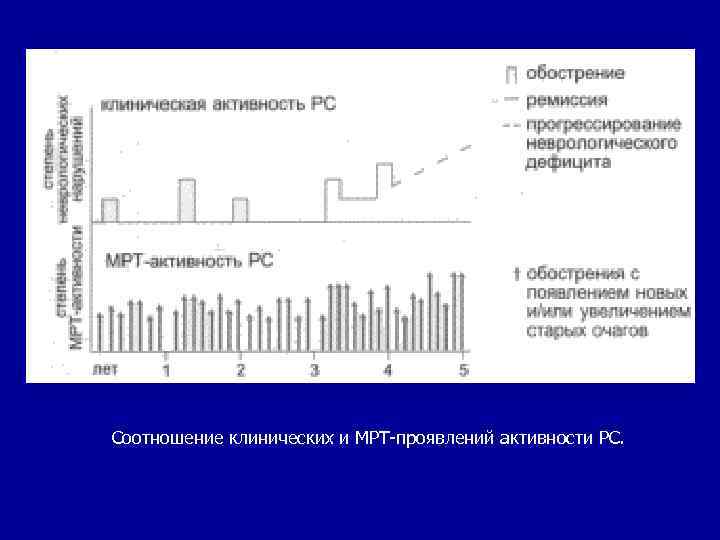

Магнитно-резонансная томография Кроме характерной локализации и формы "бляшек" на МРТ для PC характерно изменение размеров очагов при повторном исследовании с интервалом не менее 1 мес. Количество и размеры очагов не всегда соответствуют клиническому состоянию: распространенность очагов не отражает степень инвалидизации, а частота появления новых очагов на МРТ не совпадает с частотой обострений. Вероятность развития PC в течение 5 лет у больных с впервые возникшими неврологическими нарушениями, типичными для демиелинизирующего поражения ЦНС, но с нормальной картиной МРТ, не превышает 5%. Если при таких же нарушениях выявляются множественные очаги в белом веществе на МРТ, то вероятность развития PC увеличивается до 60%.

Соотношение клинических и МРТ-проявлений активности РС.